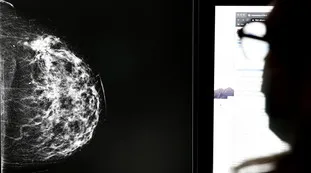

La ricercatriceTumore al seno: sperimenta una cura, se la inietta e guarisce. Una rivoluzione?12 novembre 2024